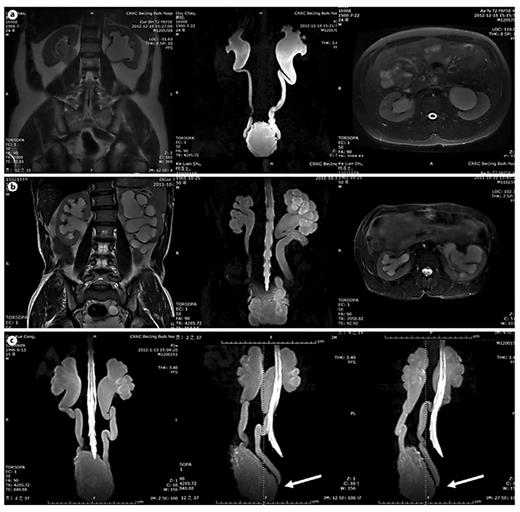

In table 1, LUTD is described according to the Guidelines of the European Association of Urology (EAU) [2] and the terminology of the International Continence Society (ICS) [5]. VUR was graded according to the IRSG, and kidney function was determined by the glomerular filtration rate from isotope renography and the serum level of creatinine. UUTD was graded as follows: grade 0, the central renal complex is closely apposed without UD (fig. 1a); grade 1, slight separation of the central renal complex exists, and the ureter is <7 mm in diameter (fig. 1b); grade 2, the renal pelvis is further dilated, a single or a few calices may be visualized and the ureter is <10 mm in diameter (fig. 1c); grade 3, the renal pelvis is dilated, there are fluid-filled calices throughout the kidney, the renal parenchyma overlying the calices has thinned (renal parenchyma loss <50%), and the ureter is tortuous and <15 mm in diameter (fig. 2a), and grade 4, similar to grade 3, but the renal parenchyma over the calices is thinned (renal parenchyma loss >50%), the ureter is severely tortuous and the ureter is >15 mm in diameter (fig. 2b). For NB patients, detrusor fibrosis and thickening secondary to progressive destruction of the bladder wall often result in ureteral strictures within the bladder wall and distal ureteral obstruction (fig. 2c), which is an important factor in the etiology of UUTD, including HN and UD, and often results in chronic renal failure. Therefore, this new system better discriminates among grade changes in UUT function, can provide objective indicators for UUT function and is an important component of long-term follow-up of conservative and surgical treatment (fig. 3).

MRU UUTD grades 3-4 and distal ureteral obstruction. a Grade 3 UUTD: MRU shows that the renal pelvis is dilated, there are fluid-filled calices throughout the left kidney, the renal parenchyma overlying the calices has thinned (renal parenchyma loss <50%), and the left ureter is tortuous and <15 mm in diameter. b Grade 4 UUTD: MRU shows that the bilateral renal pelvises are seriously dilated, there are fluid-filled calices throughout the kidneys, the renal parenchyma over the calices is thinned (renal parenchyma loss >50%), and the bilateral ureters are severely tortuous and >15 mm in diameter. c Distal ureteral obstruction: HN and UD can be displayed during 360° rotation, and vesicoureteral junction stricture or obstruction can be clearly shown (arrows: left and right ureters).